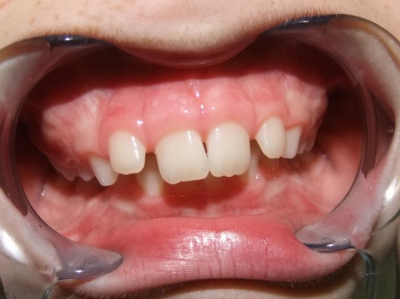

eindfoto

1-6 Bonded Hyrax + partieel vast onderkaak + TransForce onderkaak

7-13 Twinblock